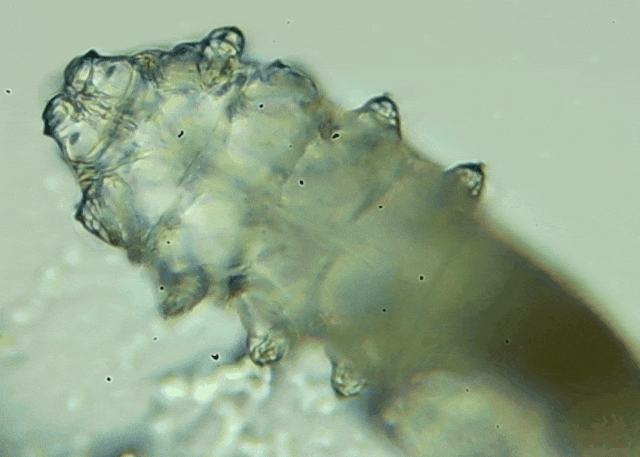

蠕形螨是一類肉眼看不見的寄生螨,常見的有毛囊蠕形螨和皮脂蠕形螨,常駐在人類的毛囊和皮脂腺里,尤其是眼睛的瞼板腺和睫毛根部。數(shù)量少時(shí),蠕形螨能與人體“和平共處”,但一旦你免疫力下降、油脂分泌旺盛或清潔不到位,他們就會(huì)以你難以想象的速度瘋狂繁殖。

而且這不是極端個(gè)案,廈門眼科中心干眼門診的臨床數(shù)據(jù)統(tǒng)計(jì),眼睛經(jīng)常紅癢發(fā)炎的人群,多數(shù)都有螨蟲,約80%以上的瞼緣炎患者螨蟲超標(biāo),一根睫毛最多能有幾十只。

睫毛上驚現(xiàn)80只螨蟲!【文章導(dǎo)讀】我只是眼睛癢,結(jié)果醫(yī)生說我睫毛里有80只蟲?這不是恐怖片,而是真實(shí)的病例:武漢一13歲男孩,右眼9根睫毛里檢出39只螨蟲,左眼9根里檢出47只。 而且這不是極端個(gè)案,廈門眼科中